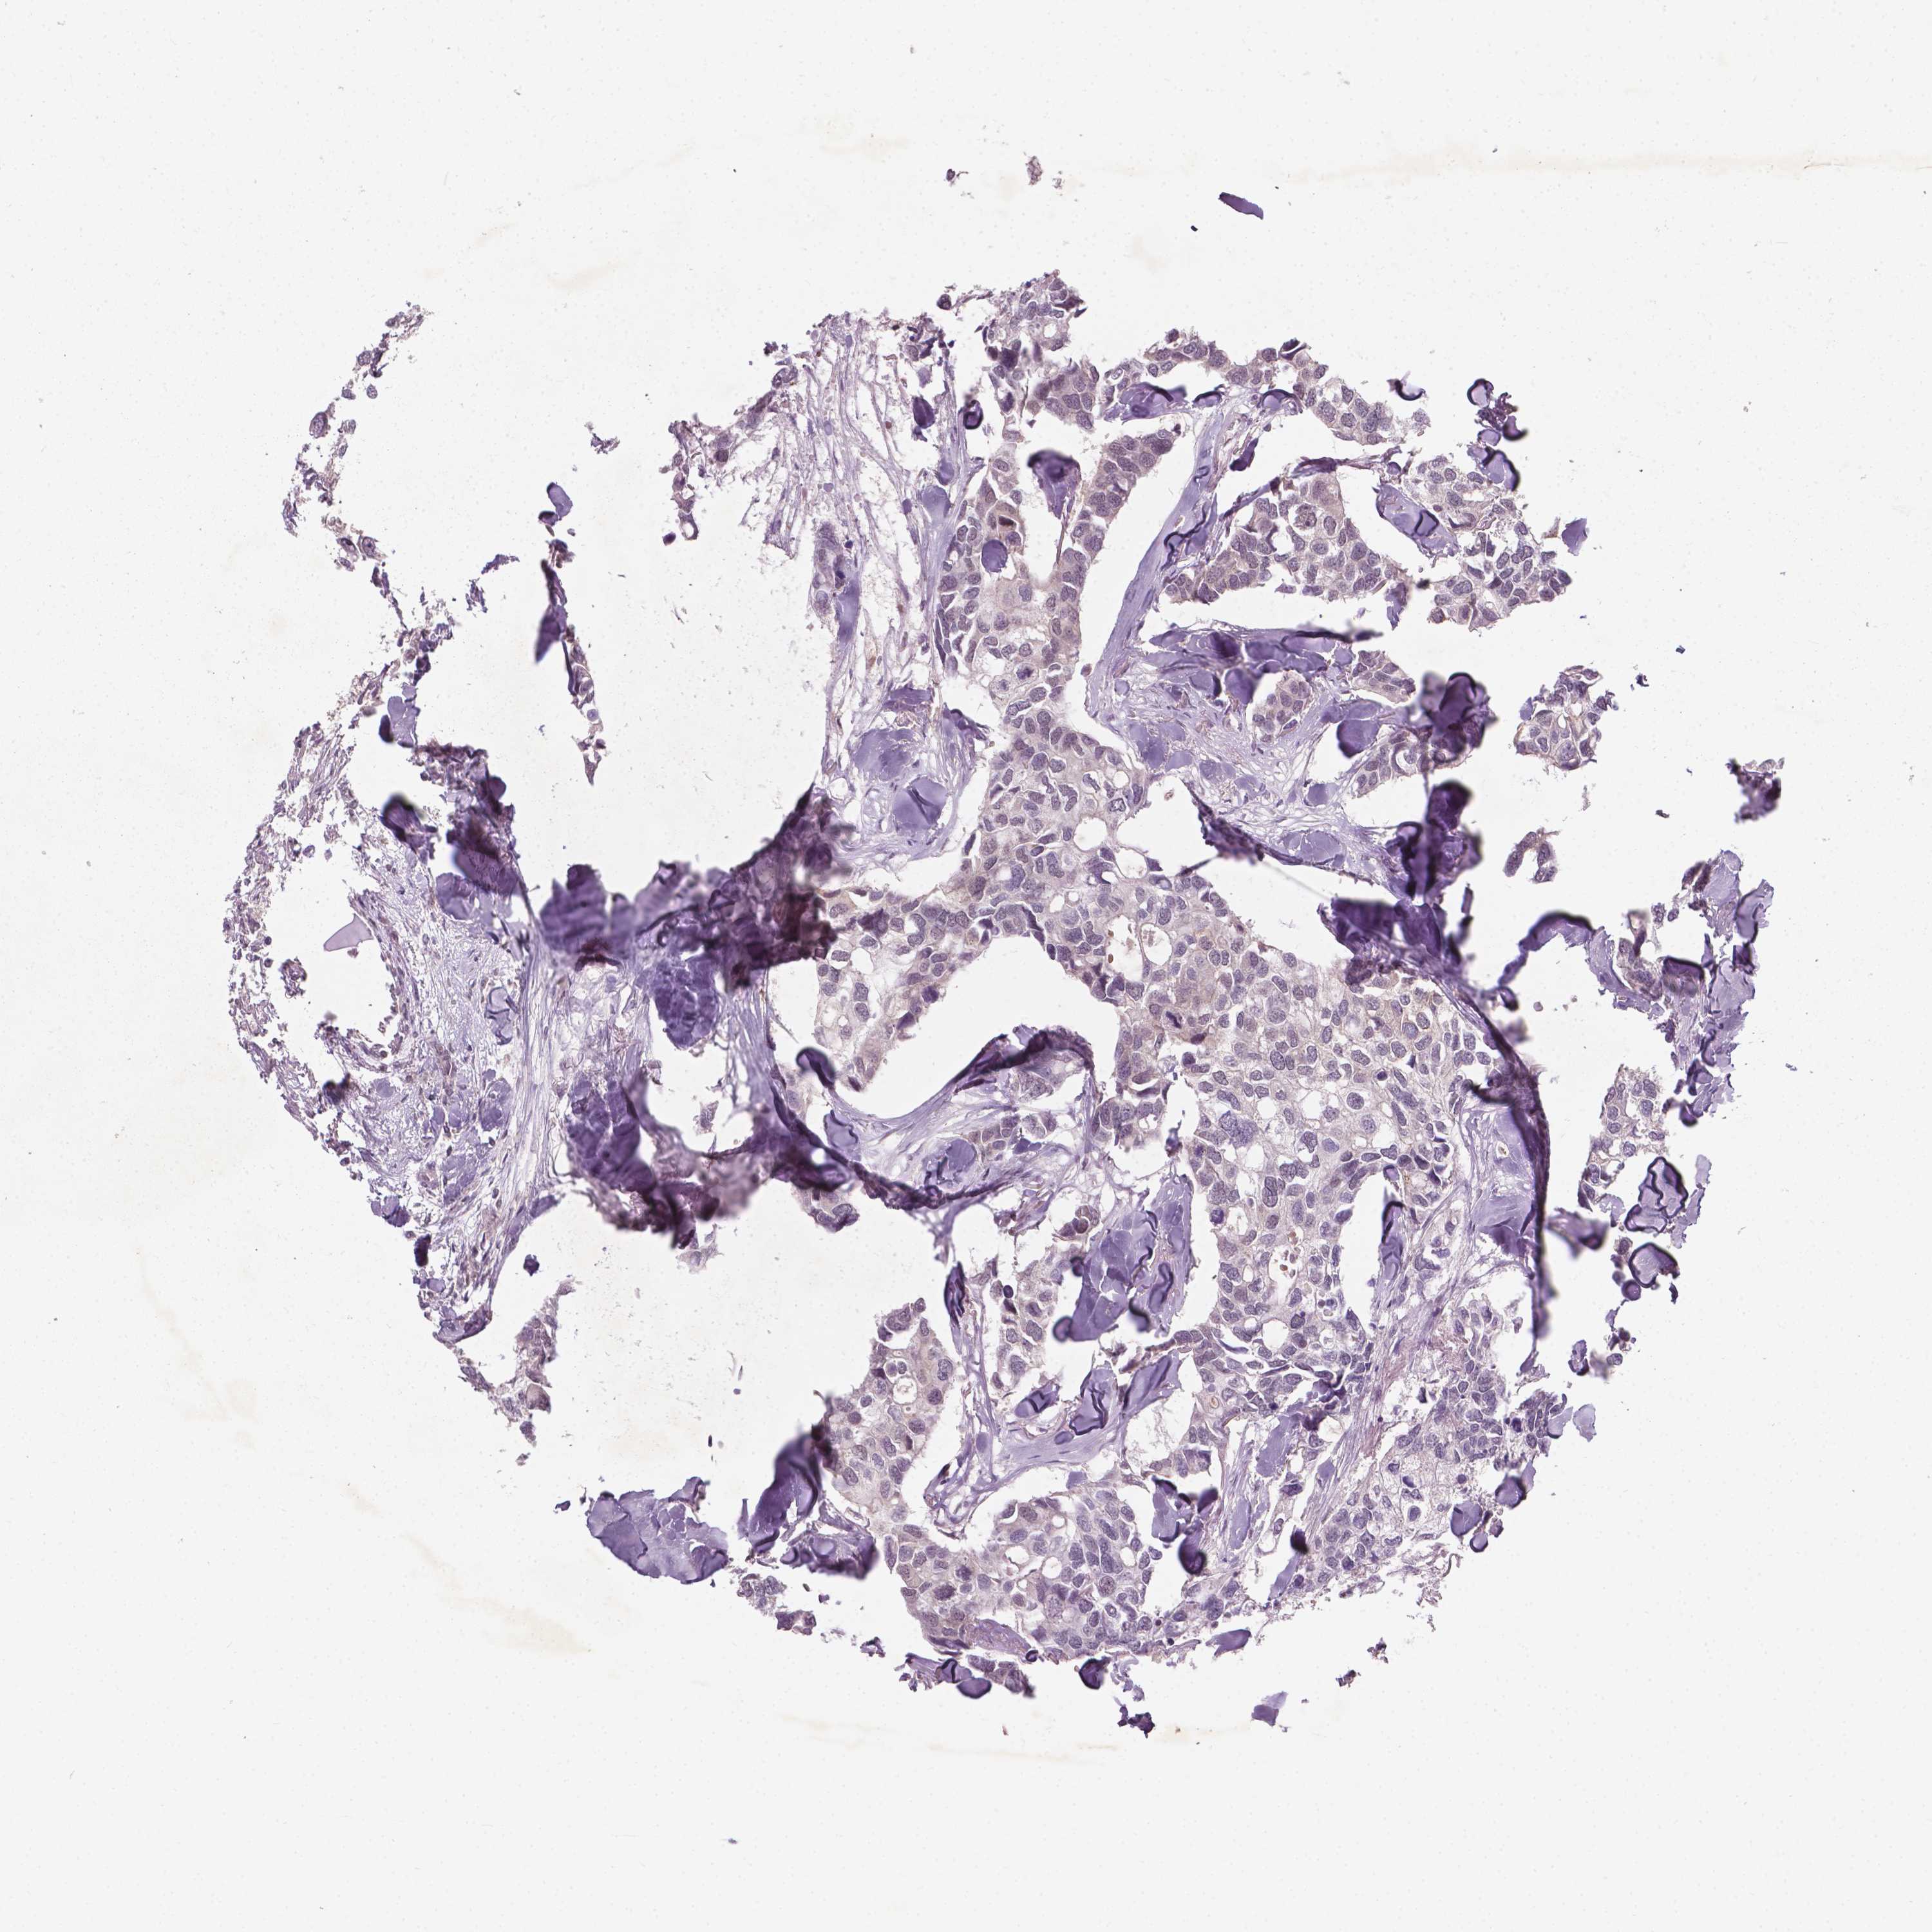

BRCA TCGA BRCA VALIDATION PROTEIN EXPRESSION

ANTIBODIES

AND

VALIDATION